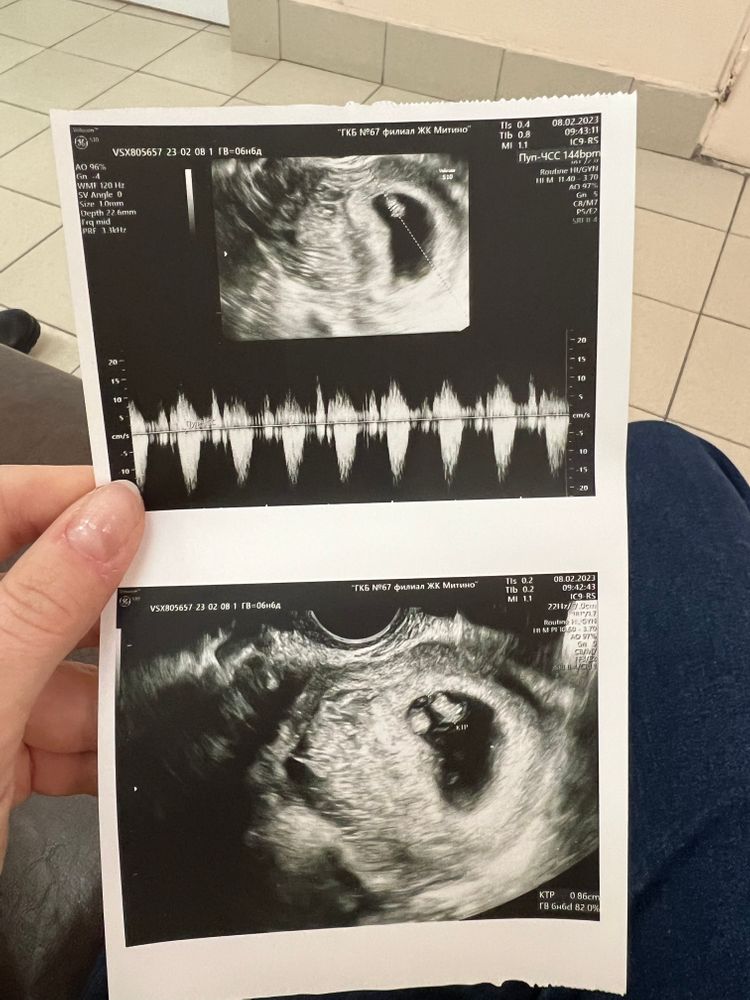

сегодня вставала на учет,сделали узи,толком ничего не сказали,дали только фотку,и поставили срок по узи как по месячным 6н6д

внизу написано ктр 0,96 или 0,86 это вообще нормальное? Беременность первая,не понимаю ничего

второе 8.02

Чсс 144, разогналось. Все отлично. А небольшие различия в днях, может погрешности узи. Срок маленький очень

Надежда, чего маленький то. 8.6 мм. Отличный ктр для этого срока. Не придумывайте